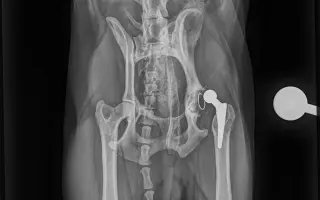

Sbírka je pro aktivního pejska Charlieho (Káju), který v říjnu 2025 podstoupil operaci cementované endoprotézy levé kyčle kvůli degenerativní coxartzróze. Samotná operace bez předoperačních a pooperačních kontrol vyšla na 64tis. Po dlouhé rekonvalescenci se opět vracel k normálnímu životu. Začalo se opět chodit na procházky, zatím ne žádné túry a vypadalo to, že vše bude v pořádku. Kontroly dopadli dobře, Charlie chodil i radostně pobíhal bez potíží. Už jsme si mysleli, že konečně bude mít klid od bolesti, ale bohužel začal náhle kulhat a chodit zadní částí těla do pravého boku. ❤️‍🩹

Nechali jsme tedy na veterině udělat orientační RTG snímky, bez přítomnosti ortopeda, byla již vidět luxace implantátu, proto jsme i během víkendu zkontaktovali MVDr. Jana Hnízda, který ho operoval a hned nás následující den pozval na RTG v sedaci. Bylo tedy zjištěno, že cement, který pojí umělou jamku s kostí se uvolnil a celý implantát jde tak v určitém pohybu do subluxace. 😥

Dorazili nám dnešní snímky, už ortopedicky přesnější